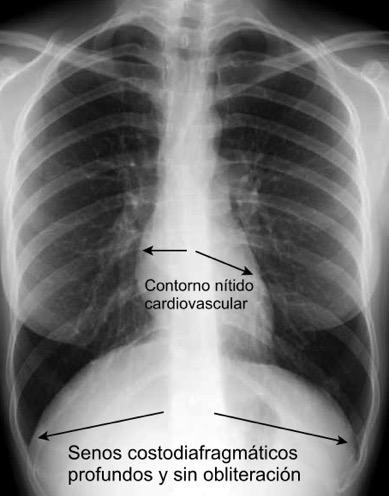

La pleura “no es visible en las radiografías PA y lateral

Se puede inferir la “normalidad “pleural si son visibles:

Senos costodiafragmáticos lateral y posteriores profundos y sin obliteración.

Cisuras interlobares (cuando son visibles), como una línea nítida, como trazada a lápiz. Contorno cardiovascular bien definido.